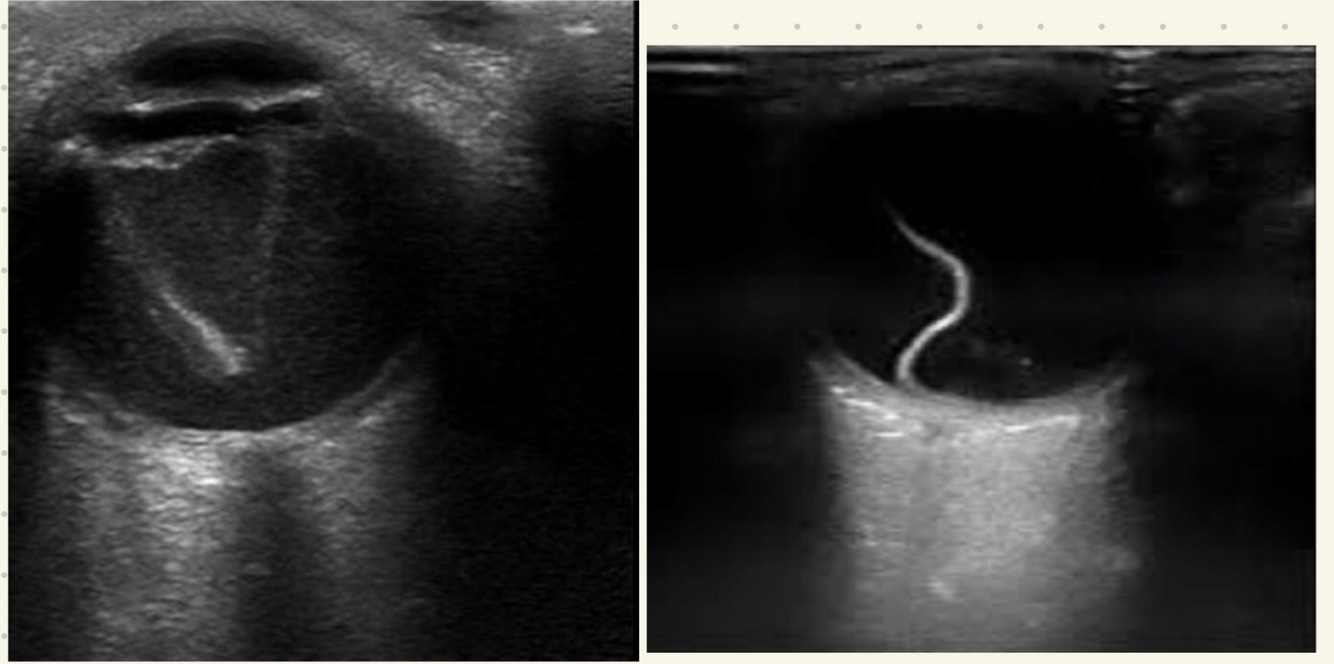

Q

¿Qué se aprecia en RB por USG?

A

Lesión hiperecogénica con calcificaciones

Dx de desprendimiento de retina:

1. Fondoscopía

2. USG/TC

Hallazgos de USG en deprendimiento de retina:

• Retina doblada y brillante

• Movimientos disminuyen con tiempo

• Forma triangular en humor vítreo (sangre)